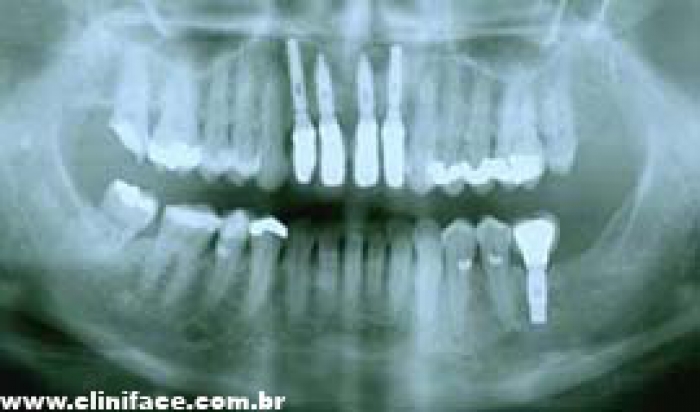

Raio X de controle, realizado em abril de 2013